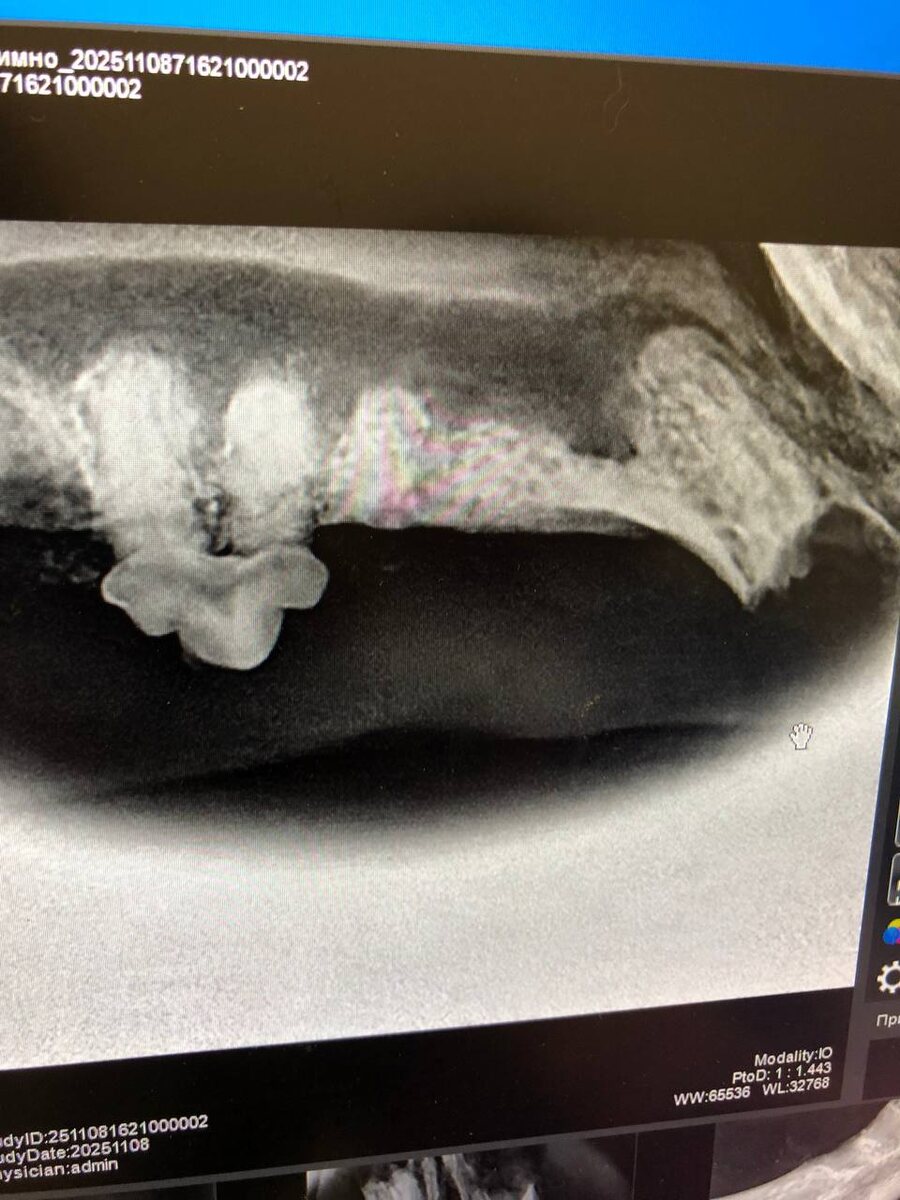

У Аси резорбция скорее все таки по II типу. Это когда как бы зубов то уже нет, но они все таки есть. Точнее их корни.

Без дентального рентгена это не увидеть.

Еще у нее уже начал устойчиво формироваться свищ на нижней челюсти, кости челюсти рыхлые, так как зубов не осталось, то и серкляж не поставить. Одна надежда, что само выправится сейчас.